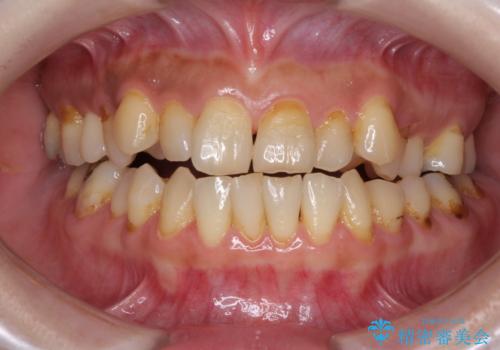

上下前歯が接触しない オープンバイトをインビザラインで改善

オープンバイト(開咬)を非抜歯インビザラインで治す